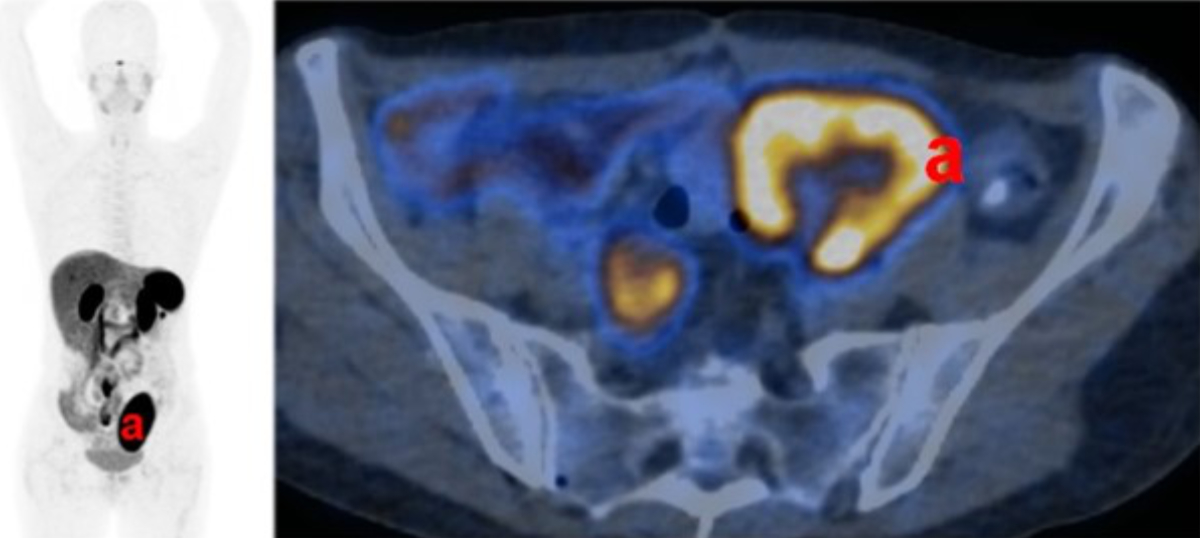

In the following months, the patient suffered from persisting fatigue, joint pain and orthostatic problems, hampering further reduction of replacement therapy. Repeated attempts to lower the dosage were only partially successful due to clinical deterioration. Fasting cortisol levels remained lower than in the immediate posttransplant course. One year after transplantation, a positron emission tomography (PET) (122 MBq Ga-68 DOTATATE) revealed a significantly reduced adrenal Somatostatin Receptor 2 (SSTR-2) positivity (figure 3).

Figure 3Adrenal graft functional activity. Functional imaging (122 MBq Ga-68 DOTATATE positron emission tomography) one year after transplantation shows strong activity in the kidney graft (a), but no signs of activity in the adrenal graft.